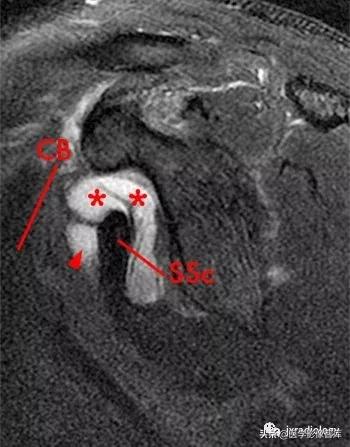

星号:superior subscapularis recess:肩胛下肌上隐窝

箭头:subcoracoid bursa:喙突下滑囊

SSc:肩胛下肌腱

小箭:middle glenohumeral ligament :盂肱中韧带

CB:喙肱肌和肌腱